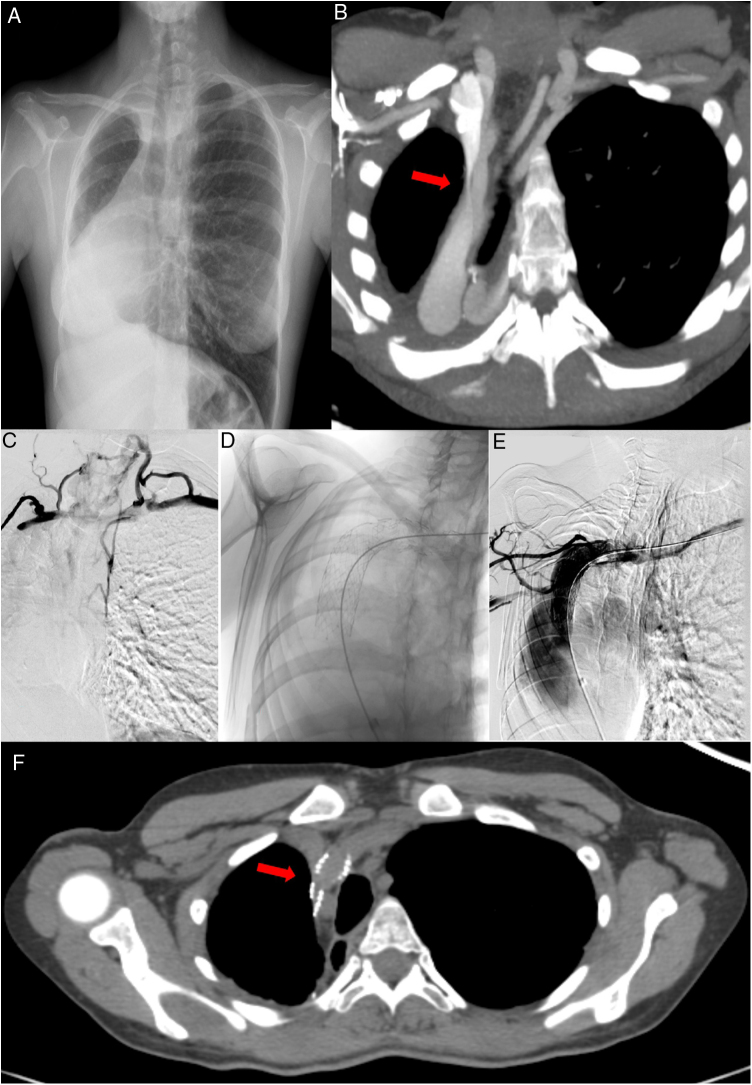

Ante la elevada sospecha clínica de SVCS, se realizaron las siguientes pruebas complementarias durante ingreso hospitalario. En la radiografía de tórax (fig. 1A), se observan cambios postquirúrgicos secundarios a neumonectomía derecha, con herniación transmediastínica e hiperinsuflación pulmonar compensatoria contralateral, sin cambios con respecto a radiografías previas. Las pruebas de laboratorio realizadas, incluido el recuento celular sanguíneo y el panel bioquímico se encontraban dentro de la normalidad. La tomografía computarizada (TC) torácica mostró (fig. 1B) una vena cava superior de morfología filiforme en su región proximal, inmediatamente posterior a la confluencia del tronco braquiocefálico derecho y la vena innominada, secundario al marcado desplazamiento mediastínico derecho y posterior. También se visualizó circulación colateral en hemitórax anterior. Estos hallazgos los confirmó el eco doppler, que mostró disminución de calibre en vena cava superior de no más del 50% morfológicamente, aunque dicha estenosis aumentaba con el decúbito.

A) Radiografía de tórax PA. Neumonectomía derecha, herniación transmediastínica e hiperinsuflación pulmonar compensatoria contralateral. B) TC con CIV. Reconstrucción MIP. Estenosis a nivel proximal de la VCS. C) Flebografía. Estenosis objetivada mediante instilación de contraste intravenoso a nivel proximal de la VCS y circulación colateral. D) Imagen obtenida por radioscopia. Prótesis normoposicionada a nivel proximal de la VCS, inmediatamente posterior a la confluencia del tronco braquiocefálico derecho y la vena innominada. E) Flebografía. Reperfusión de la región estenótica de la VCS. F) TC con CIV. Reconstrucción MIP. Reperfusión de la VCS tras el implante de la prótesis vascular.

Tras valorar el caso en sesión multidisciplinar (incluyendo cirujanos torácicos, unidad de broncoscopia, unidad de FQ, radiología vascular, oncología radioterápica, etc.) se decidió implantar una prótesis vascular de forma percutánea. Se realizó una flebografía selectiva de ambos miembros superiores que demostró importante estenosis de la vena cava superior inmediatamente distal a la confluencia de los troncos innominados con abundante circulación colateral (fig. 1C) y se procedió a la colocación de una prótesis auto expandible híbrida, tipo sinus-venous de 18 mm de diámetro con buenos resultados en el control inmediato (fig. 1D). Tras la intervención, la circulación colateral fue disminuyendo hasta casi resolverse al momento del alta, así como el edema en la región facial y extremidades superiores. Requirió de doble antiagregación durante seis meses para prevenir la re-estenosis de la prótesis, manteniendo posteriormente de forma indefinida ácido acetilsalicílico. En el control radiológico, mediante TC torácica con contraste intravenoso (CIV) a los dos meses del procedimiento vascular, se comprobó normoposicionamiento de la prótesis y permeabilidad de esta (fig. 1E). En el seguimiento, que alcanza la actualidad, la paciente no ha presentado ninguna complicación hemorrágica ni existe compromiso de la permeabilidad de la prótesis.